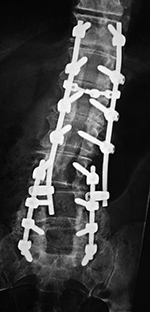

| Extensive lumbar spine fusion with pedicle screws and rods |

| A laminectomy has been performed from T12-L5. Pedicle screws and rods are at L3-S1 from the initial lower lumbar spine fusion. Later surgery added pedicle screws and rods at T12-L3, and L3-L5 with a crosslink at L2. |